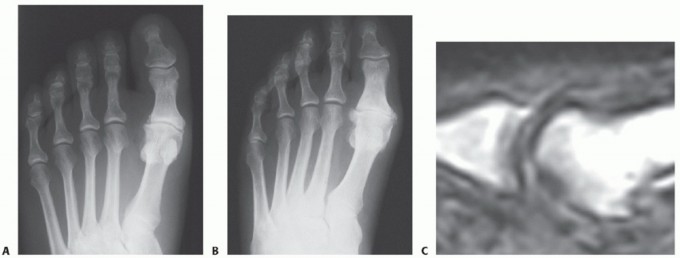

DEFINITION Sesamoiditis is a general term that indicates an injury to the sesamoid bone. There are multiple p…